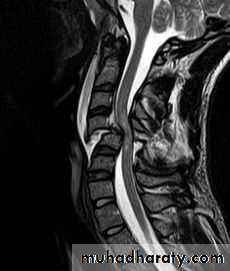

DIAGNOSISX RAY

Anterio posterior X ray radiograph.lateral radiographs with the head in flexion and extension may revealinstability that is not shown in the routine lateral film.

through the open mouth.Computed tomography (CT)

and magnetic resonance imaging (MRI).

Flexion and flexion-rotation injuries

flexion alone tends to a wedge compression fracture .whereas combined flexion and rotation cause subluxation ,

dislocation or fracture-disIocation.A flexion or flexion-rotation force may also cause massive displacement of an intervertebral disc, without bone injury